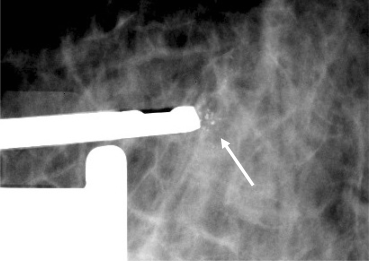

Figuur 4

Opname van stereotactische benadering van gegroepeerde calcificaties (pijl) met de biopsienaald ter plaatse.

Indien er een afwijking is op het mammogram die niet te herkennen is met echografie, is het mogelijk om met behulp van stereotaxie toch een biopsie te verrichten. Denk hierbij aan suspecte calcificaties in de mamma, een gebied met architectuurverstoring of een massa die te klein is om goed te kunnen worden onderscheiden met echografie.

Een stereotactische procedure kan zowel in zittende als in liggende positie plaatsvinden. De borst wordt gecomprimeerd en vanuit twee hoeken gefotografeerd, waardoor de exacte locatie van de afwijking kan worden berekend (fig. 4). Aansluitend worden er (vacuümgeleide) biopten genomen en wordt de biopsielocatie meestal voorzien van een marker/clip, zodat de chirurg de locatie kan terugvinden.